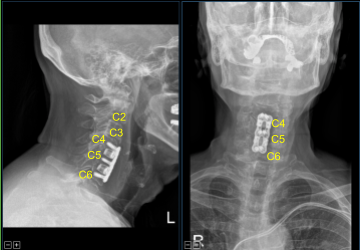

La PA y la fluoroscopia lateral mostraron un posicionamiento correcto. Los potenciales evocados motores mostraron una ligera disminución de la amplitud en el C5-6 derecho. La instrumentación fue entonces retirada. El espacio de instrumentación se limpió y se regó al ras.

No hubo cambios significativos, por lo que se reemplazó el espaciador intercorporal. Los osteofitos anteriores se enjuagaron con un taladro eléctrico de alta velocidad. La hemostasia se obtuvo con cera ósea. La placa lordótica de titanio se colocó de C4 a C6 y se aseguró con un pasador.

La fluoroscopia mostró el tamaño y la posición correctos, por lo que se aseguró con seis tornillos de titanio de 14 mm decorticados con un taladro eléctrico de mano de 12 mm. La PA y la fluoroscopia lateral mostraron buen posicionamiento. Todos los tornillos se apretaron finalmente utilizando un dispositivo integrado en la placa.